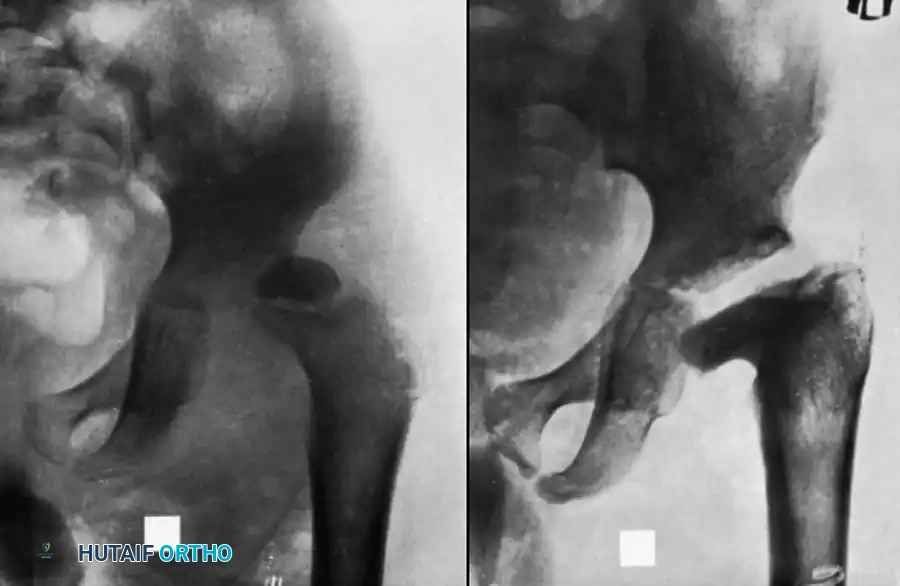

Pathological Dislocation

Pathological dislocation is predominantly a pediatric complication, rarely seen in adults. It occurs due to the combination of massive capsular distension from purulence, ligamentous laxity induced by hyperemia, and severe reflex muscle spasms.

If the dislocation is recognized early—before severe soft-tissue contractures develop—reduction is usually accomplished easily at the time of surgical drainage. The hip is then stabilized in a spica cast, and satisfactory long-term function may result.

However, if the diagnosis is delayed and the femoral head has been damaged by infection or ischemia, immediate manipulation is contraindicated. Attempting closed reduction on a compromised, osteopenic proximal femur carries a high risk of iatrogenic femoral neck fracture. Instead, skeletal traction should be applied via a distal femoral pin. Traction is gradually increased until radiographic imaging confirms the femoral head has been pulled down to the level of the acetabulum. Only then is the dislocation reduced via gentle abduction and internal rotation. Post-reduction, the hip is immobilized in a spica cast until stability is achieved or until fibrous/bony ankylosis develops.

Clinical Pearl (Lloyd-Roberts): In infants, severe osteopenic changes in the femoral head associated with acute septic arthritis can mimic complete joint destruction on plain radiographs. What appears to be a dislocation with total destruction of the proximal femur may actually be a viable femoral head that has simply demineralized. These hips should be explored or gently manipulated, as the head may survive and remodel once reduced and the infection cleared.